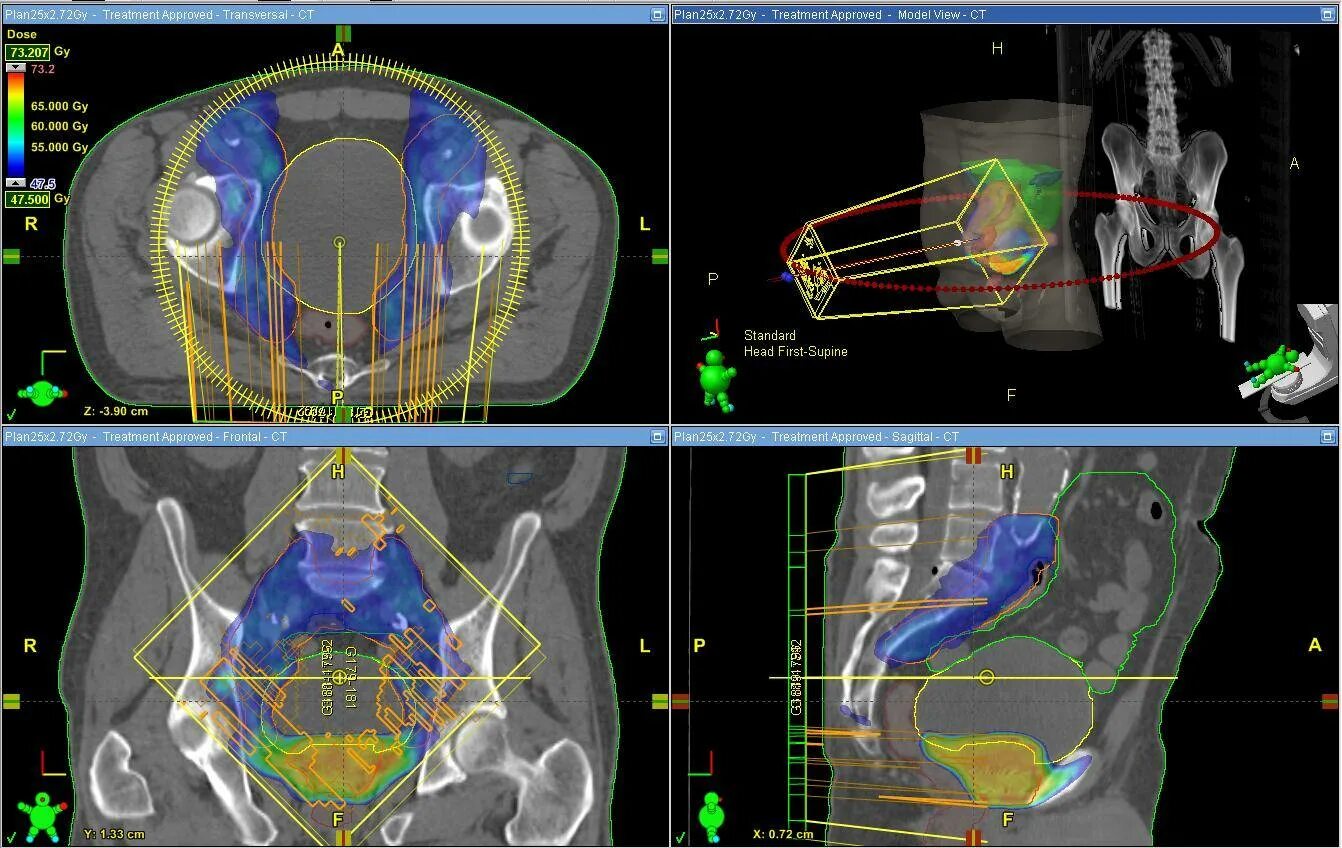

Аппарат для лучевой терапии тиратрон. imrt лучевая терапия.

Брахитерапия гамма-нож. imrt лучевая терапия предстательной железы. облучение при онкологии.

Лучевая терапия с визуальным контролем. igrt лучевая терапия. дистанционная лучевая терапия предстательной железы. линейный ускоритель для лучевой терапии предстательной железы.

Трехмерное планирование лучевой терапии. трехмерная конформная лучевая терапия. vmat лучевая терапия. imrt лучевая терапия шейки матки.